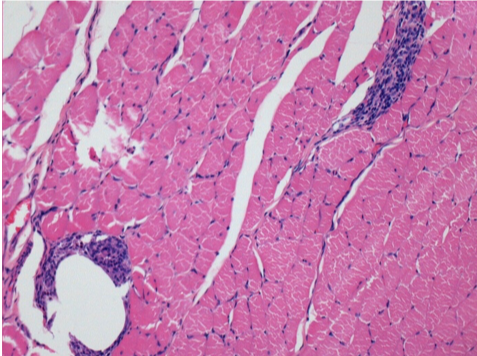

3 meses (D90) después de la inyección de Endopeel 0.1ml en el músculo pretibial derecho.

09